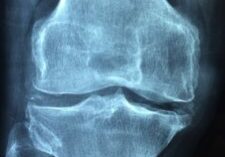

Arthritis

Arthritis is a joint disorder and can occur in areas ranging from the spine, fingers, wrist, knees, and more. It can occur due to trauma or infection of the joint or simply from age. Arthritis pain is caused by inflammation, damage from disease, and painful stiffness of joints.  Pain from arthritis is typically constant and…